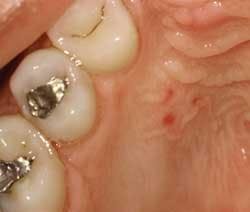

Perioral and intraoral characteristics: The size of each of the three clinical descriptions may vary and may be seen in one patient who exhibits all three classifications (see Figure 2). Because the lesion is caused by hemorrhages (pooled blood) within the tissues, the lesions will not blanch when diascopy is applied (diascopy is using a glass slide to apply pressure to the area of concern). If the flow of blood is disrupted, a vascular type lesion would be considered in a differential diagnosis. If the area of concern is in a difficult location where diascopy would not work, simply using the mirror to disrupt blood flow may be used.